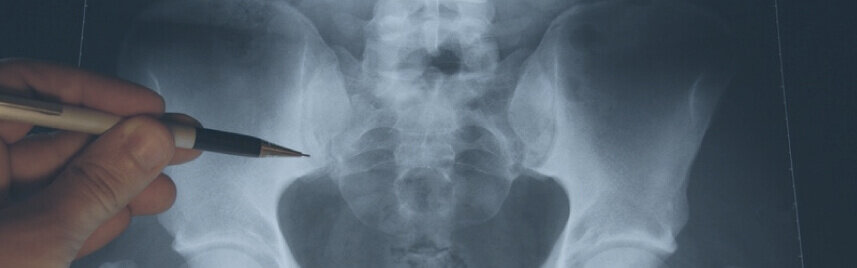

Нестабильность позвоночника — патология, связанная с длительной перегрузкой и ослабленностью мышц позвоночника, характеризующаяся наличием избыточной подвижности (соскальзывания) одного позвоночного сегмента относительно другого (более 5 мм).

Слабая нестабильность выявляется при правильной диагностике (при выполнении функциональных рентгенограмм позвоночника) и лечится путём физиотерапии и укрепления мышц каркаса позвоночника в целях предотвращения болей и дальнейших осложнений.